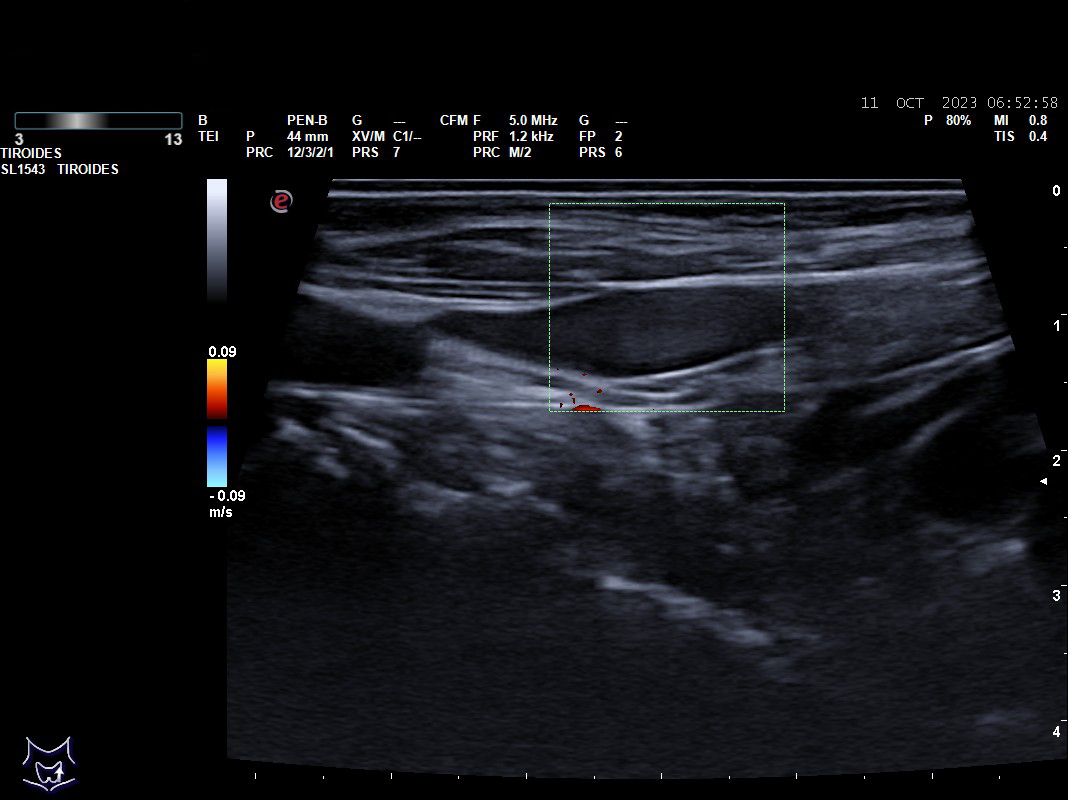

Hallazgos ecográficos: nódulos tiroideos subcentimétricos sin cambios, yugular interna izda con contenido discretamente hiperecogénico que no capta Doppler y colapsabilidad incompleta.

Se deriva a urgencias es valorada por cirugía vascular quienes describen la presencia del trombo sin poder precisar su final y se ingresa a la paciente ya que el servicio de radiología no considera realizar en ese momento el estudio pertinente.